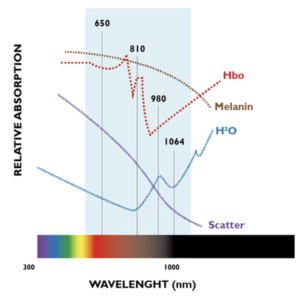

Hamblin nel 2006 ha definito un range di lunghezze d’onda ( articolo “𝑴𝒆𝒄𝒉𝒂𝒏𝒊𝒔𝒎 𝒐𝒇 𝑳𝒐𝒘 𝑳𝒆𝒗𝒆𝒍 𝑳𝒂𝒔𝒆𝒓 𝑻𝒉𝒆𝒓𝒂𝒑𝒚”) che hanno potere di penetranza ottimale e che non vengono eccessivamente assorbite dai principali cromofori, garantendo un assorbimento ottimale da parte del tessuto al fine di ottenere un valido scambio di energia con lo stesso.

Dal grafico di deduce quali siano le lunghezze d’onda utili e come queste interagiscono con i principali cromofori.

Ecco perché con lunghezze d’onda diverse ottengo processi diversi.

- 650 nm

- Assorbito principalmente dalla melanina, garantisce un notevole scambio di energia in superficie e nella media profondità. Inibisce la proliferazione batterica e favorisce crescita cellulare, consentendo di ottenere risultati sorprendenti nel trattamento di ferite, piaghe e ulcere.

- 780 nm

- Il suo assorbimento consente il processo di ossidazione dell’emoglobina per accelerare la produzione di ATP. Questa lunghezza d’onda ha dimostrato scientificamente la sua efficacia nella rigenerazione del nervo

- 810 nm

- Consente una rapida attivazione del processo ossidativo dell’ emoglobina, accelerando la produzione di ATP. Muove la giusta energia per fornire ai muscoli e tendini aiuti di rigenerazione dei tessuti.

- 980 nm

- Assorbito principalmente dall’acqua, permette di ottimizzare l’azione sui termocettori e meccanocettori. Quando combinato con una modalità di emissione di impulsi laser di potenza, durata e frequenza variabile, interagisce correttamente con il sistema nervoso periferico generando un veloce e lungo effetto analgesico duraturo, rimuovendo il dolore in modo rapido e sicuro per attivare il meccanismo Gate Control al fine di un rapido effetto antalgico.

- 1064 nm

- La sua elevata direzionalità permette di veicolare la corretta dose di energia direttamente alla noxa. Il risultato è una perfetta sinergia che armonizza l’effetto analgesico rapido con un controllo dei processi infiammatori negli strati profondi e un’attivazione dei processi metabolici vitali per tutte le attività cellulari.

- 1210 nm

- Altamente assorbito dall’acqua, l’energia trasmessa viene convertita in calore. Gli strati di tessuto profondo diventano punti di calore localizzati, creando gradienti termici cellulari che stimolano microcircolazione cellulare e ossigenazione.